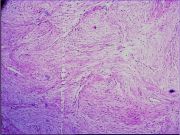

| 2021年12月10日 (五) 13:16 | 14号切片-纤维肉瘤-镜下观6.jpg (文件) |  |

135 KB | Cirno.9 | 基于MsUpload的文件上传 | 1 |

| 2021年12月10日 (五) 13:16 | 14号切片-纤维肉瘤-镜下观5.jpg (文件) |  |

139 KB | Cirno.9 | 基于MsUpload的文件上传 | 1 |

| 2021年12月10日 (五) 13:16 | 14号切片-纤维肉瘤-镜下观4.jpg (文件) |  |

125 KB | Cirno.9 | 基于MsUpload的文件上传 | 1 |

| 2021年12月10日 (五) 13:15 | 14号切片-纤维肉瘤-镜下观3.jpg (文件) |  |

193 KB | Cirno.9 | 基于MsUpload的文件上传 | 1 |

| 2021年12月10日 (五) 13:15 | 14号切片-纤维肉瘤-镜下观2.jpg (文件) |  |

143 KB | Cirno.9 | 基于MsUpload的文件上传 | 1 |

| 2021年12月10日 (五) 13:15 | 14号切片-纤维肉瘤-镜下观1.png (文件) |  |

519 KB | Cirno.9 | 基于MsUpload的文件上传 | 1 |